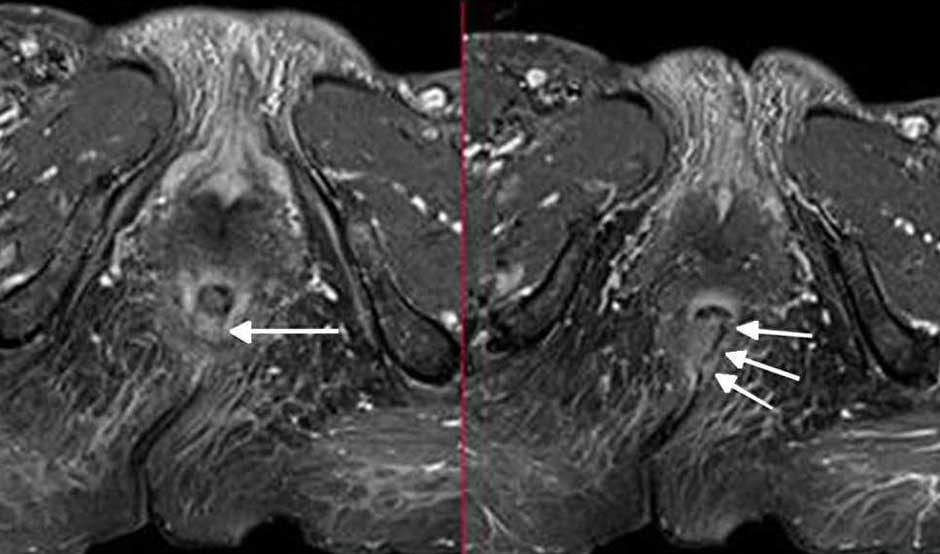

Una de sus conclusiones es que "el bloqueo del nervio pudendo guiado por imágenes es seguro, eficaz y bien tolerado con pocas complicaciones". En este sentido, los autores advierten que un bloqueo exitoso del nervio pudendo es crucial para el diagnóstico de la neuralgia del pudendo y proporciona orientación para el tratamiento. "Diferentes estudios, incluidos dos ensayos controlados aleatorios, demostraron la ausencia de complicaciones para este procedimiento. Además, no se demostró ninguna diferencia significativa en términos de eficacia entre la ecografía y la guía fluoroscópica", sentencian.